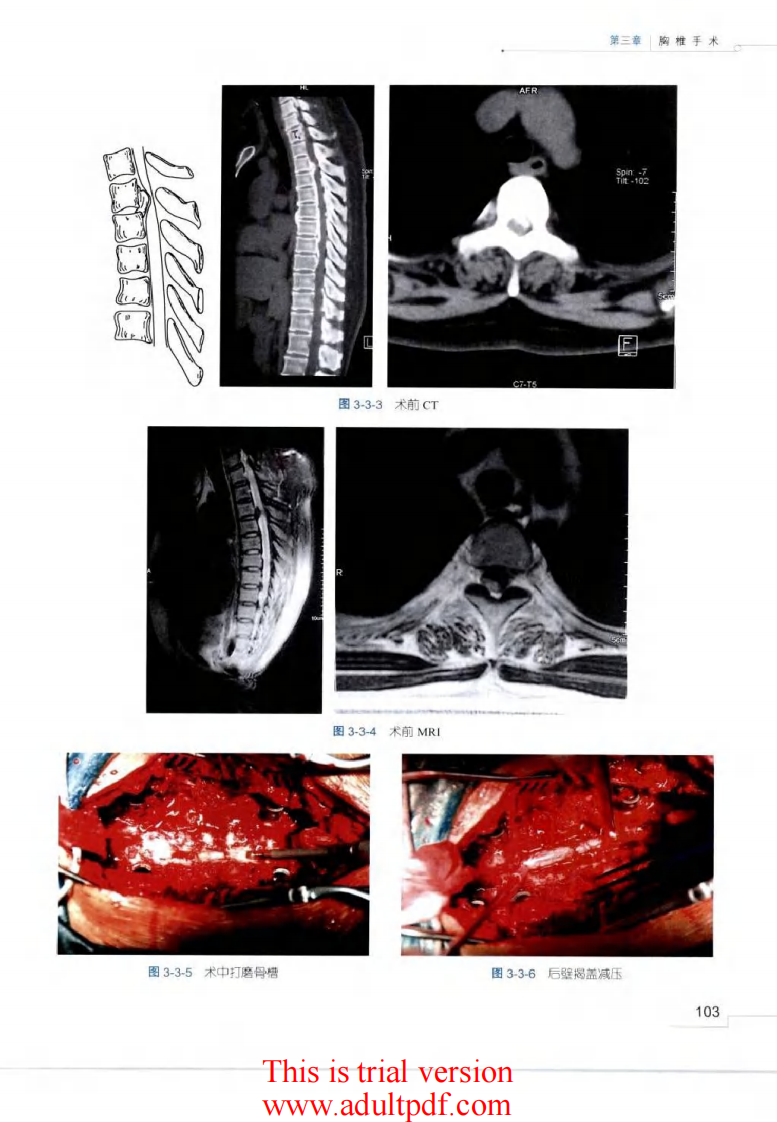

脊柱外科手术操作与技巧(骨科手术技巧丛书)3.pdf